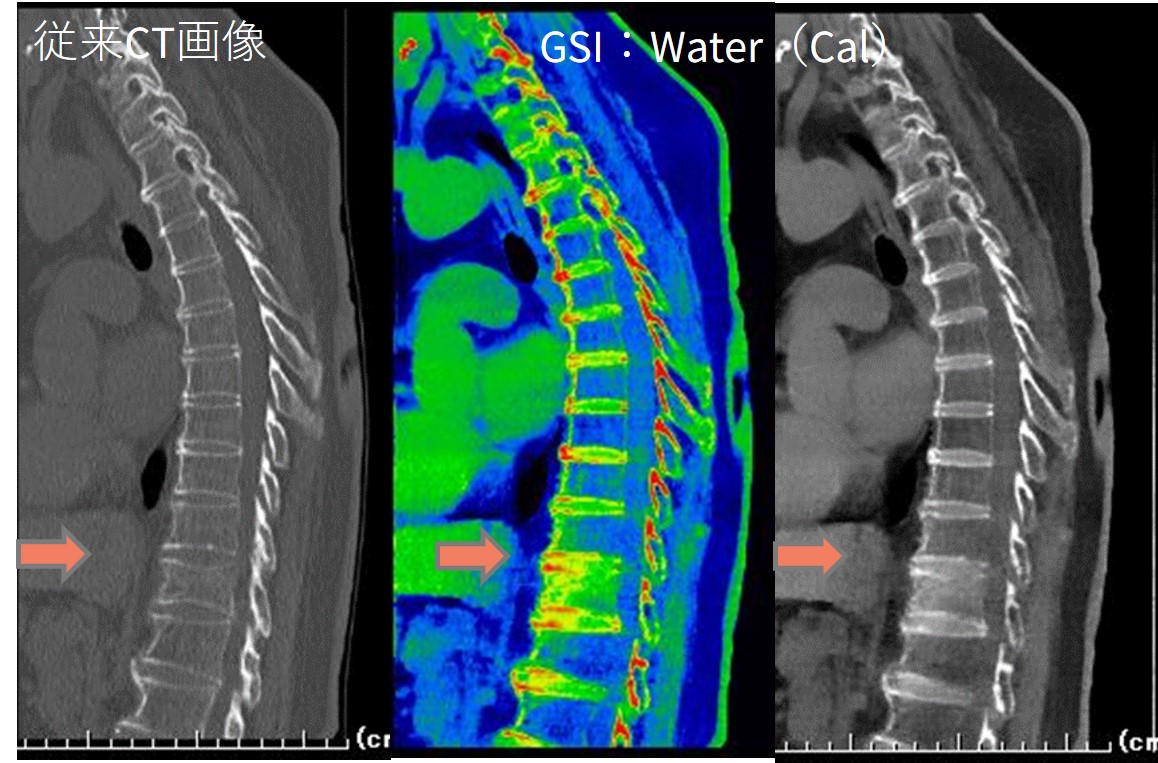

当院では、 Revolution CT導入を機に、造影検査はRevolution CT優先へ変更し、すべての造影検査をGSI(ガーネット検出器を使った超高速kVスイッチングのデュアルエナジー検査)にて撮影しています。ルーチン的に出力している画像は、68kev画像と、ヨード密度画像を自動作成しており、状況に応じて様々がな画像を提供しています。救急対応ではGSI撮影を優先することでCT担当のすべての技師がRevolution CTの操作とAWSによるGSI画像処理可能となりました。救急担当の医師からも『DEで』『デュアルで』といったコメントが入るようになり、積極的にGSI撮影を行っています。特に脊椎圧迫骨折等整形領域は従来のCT画像では圧迫骨折の有無は不明なことも多く、必ずMRI検査も施行したうえで診断されていました。

現在はGSI撮影による水密度強調画像から圧迫骨折の新旧の判別ができ、MRIの前に診断がつくと評価されています。(Fig1)

77歳女性

検査コメント:

「転倒し腰背部痛主訴の方の骨折否定目的です。

よろしくお願いします。デュアルもお願いします。」

整形外科:

Th12新規骨折と診断され、MRI追加検査なし

Fig1. 胸椎の通常CT画像とGSI画像比較